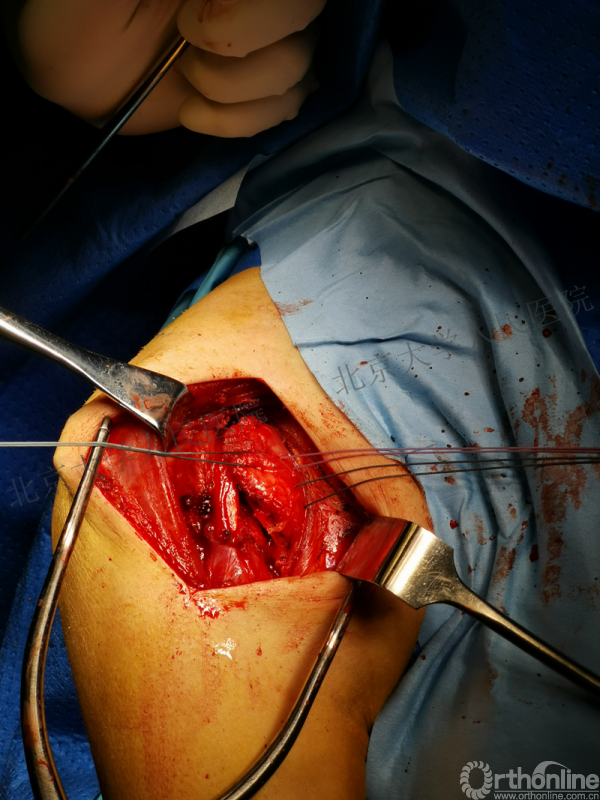

全麻下行切开复位内固定术,备植骨+关节镜检

胸大肌三角肌间隙入路

操作步骤

术后影像学检查